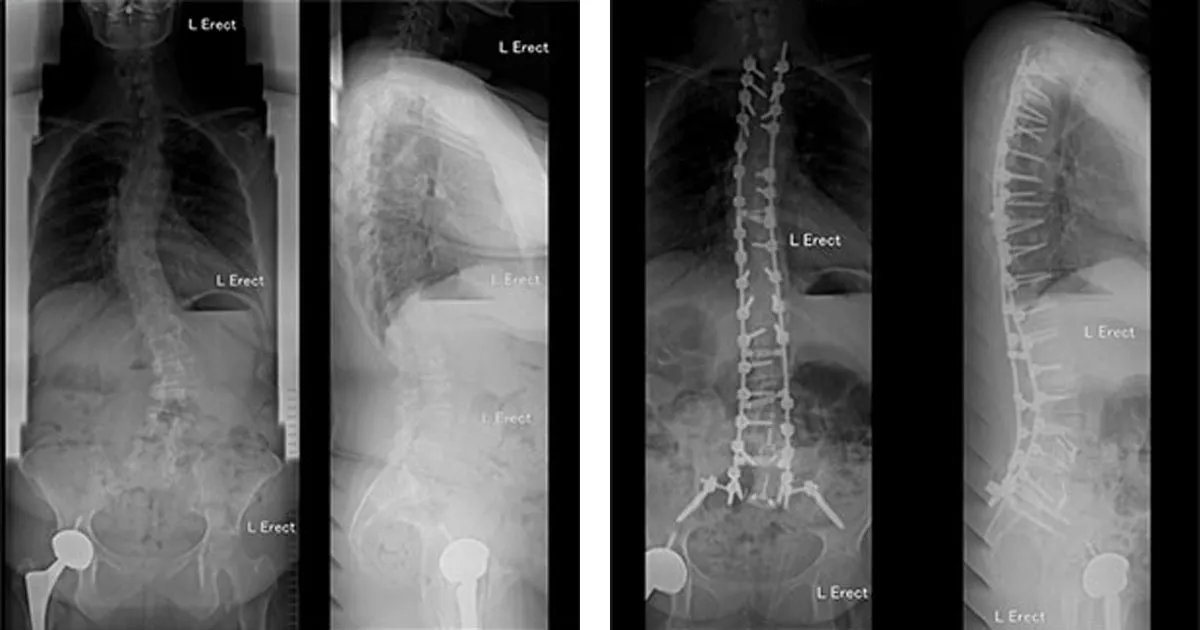

Image above: Before (L) and After (R) Dual Surgery Deformity Surgery